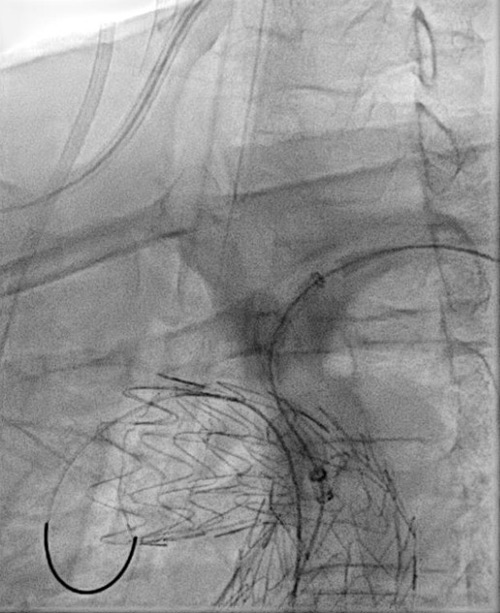

Step 1

GORE® TAG® Thoracic Branch Endoprosthesis (TBE)

Challenging branch take-offs may require specific angulations!

Step 1: result

- TBE in 1st step followed by two TEVAR components after 8 weeks.

37 TAG® Conformable in 37 TBE -> Long overlap!

Staged deployment of the tapered TAG® Conformable with precise control of the distal landing zone.

Ballooning under controlled hypotension with a Tri-Lobe balloon.